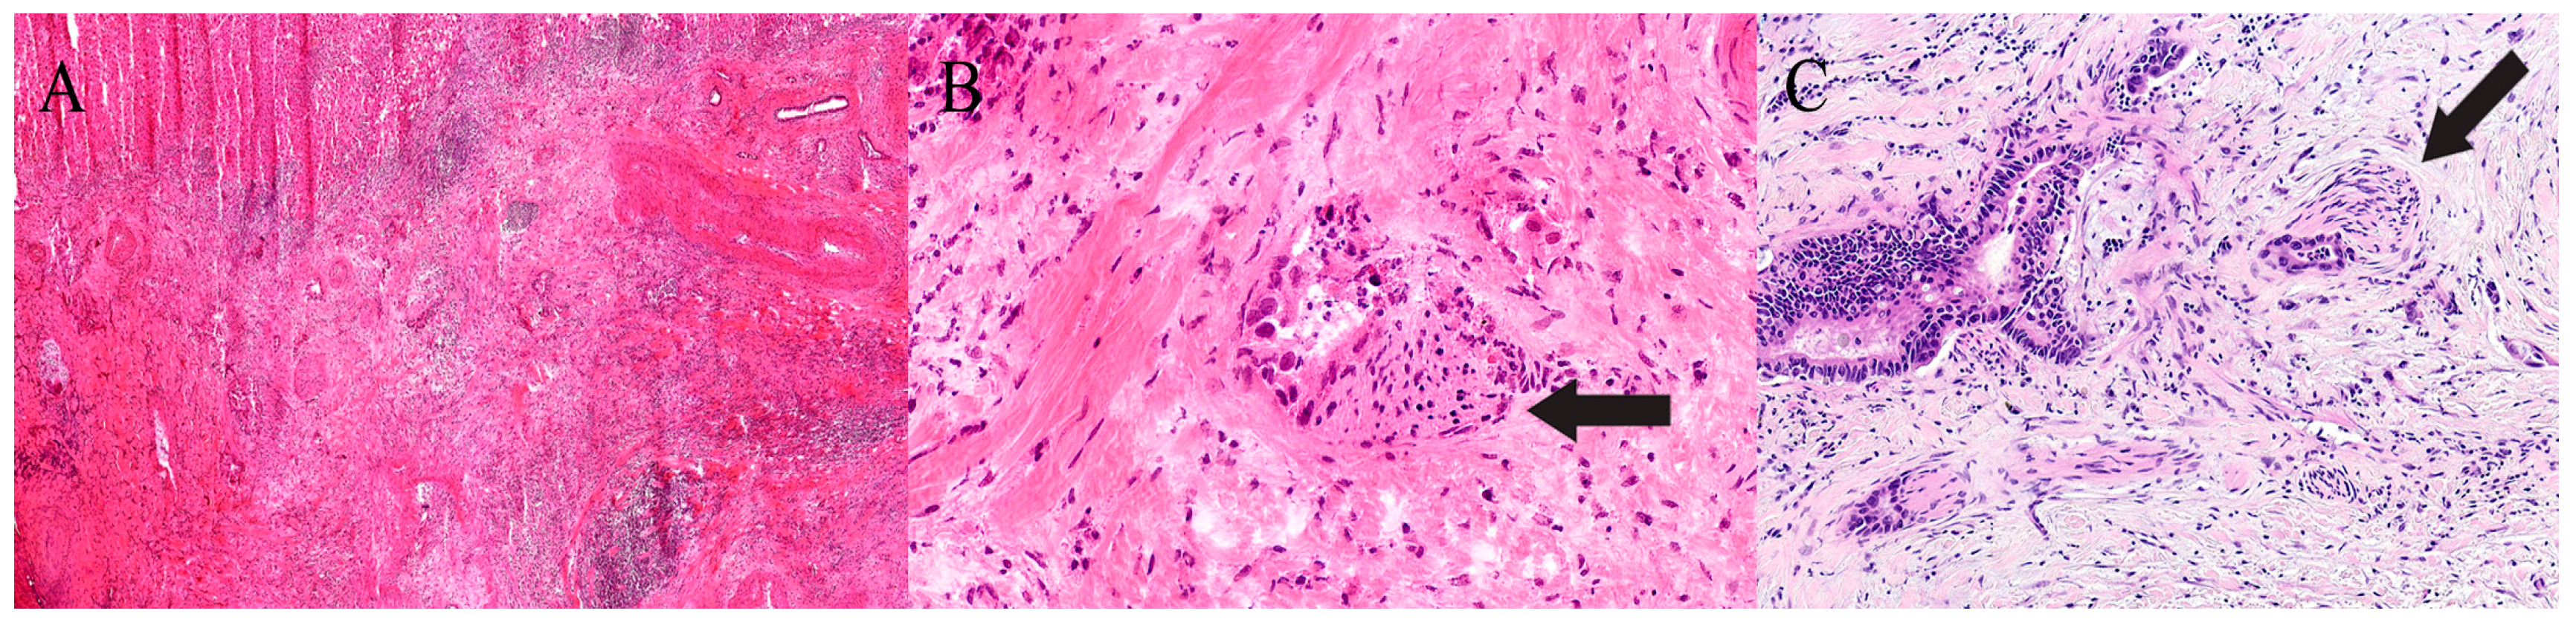

Analytical errors are the most frequent and may stem from non-representative or suboptimal sampling, difficulty cutting calcified or fibrotic tissue (Figure 3), or loss of tissue during freezing. Artefactual distortion—most often from freezing, tissue compression, or incomplete embedding—can obscure cytologic and architectural detail, predisposing to misinterpretation. Interpretative errors include misclassification of benign versus malignant lesions, incorrect tumour typing, or inaccurate margin assessment. The time-sensitive environment of intraoperative consultation and inherently limited tissue quantity amplify these risks, underscoring the need for cautious correlation with permanent sections.

In the oesophagus, the predominant pathologies include adenocarcinoma (tubular or poorly cohesive types), squamous cell carcinoma, and Barrett’s oesophagus [58]. Less common spindle cell lesions such as gastrointestinal stromal tumours (GISTs) or granular cell tumours may also occur [59]. Gastric pathology most often represents adenocarcinoma (Figure 4) [60], with occasional GISTs (Figure 5) [61] and rarer lymphoproliferative disorders, including MALT lymphoma and diffuse large B-cell lymphoma [62].

Histologic features supporting adenocarcinoma include nuclear pleomorphism, disorganised ductal architecture, incomplete lumina, infiltrative single cells, and perineural invasion—the latter being a particularly strong indicator of malignancy (Figure 8). Diagnostic overlap with chronic pancreatitis or therapy-related changes, however, can make interpretation difficult (Table 3) [87].